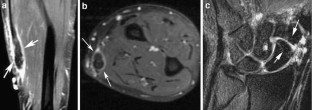

Results

Five of the patients showed evidence of triscaphe osteoarthritis. One of the patients showed synovitis and reactive marrow edema at the triscaphe joint without more specific findings of osteoarthritis. Five patients showed evidence of FCR tenosynovitis. Partial-thickness tears were noted in three patients. Two patients showed complete discontinuity of the FCR; one of them had undergone prior tendon harvesting for interposition arthroplasty after trapezectomy. One patient showed a ganglion cyst in connection to the FCR tendon sheath.

The FCR tendon courses over the volar surfaces of the scaphoid and trapezium in a separate fibro-osseous tunnel. This anatomical and functional relationship explains the coexistence of FCR tendinopathy and STT arthritis demonstrated by MR imaging.